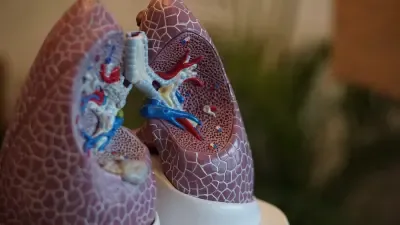

Can Inhaling Agricultural Dust Endanger Gut Health?

A recent study reveals alarming findings about agricultural dust and its potential dangers to gut health in animal agriculture workers. This research highlights the need to understand the broader…